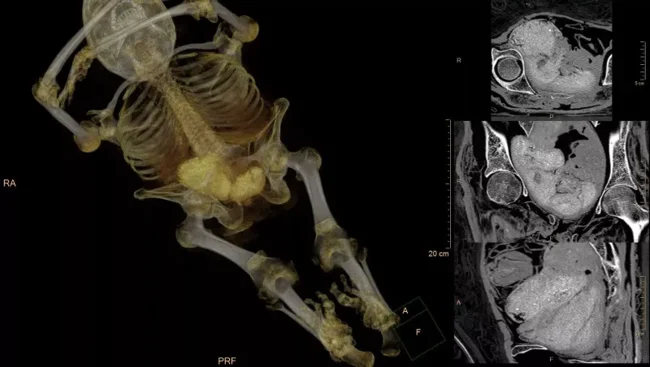

They decided to check this only in 2015. And for good reason. The CT images did not reveal anything that resembled male genitalia. But they clearly saw thick long hair and — mammary glands.

For a more detailed analysis, they scanned the abdominal cavity of this woman, who died between the ages of 20 and 30.

"When we saw a small leg, and then a small hand, we were really shocked," anthropologist Marzena Ozarek-Schilke, head of the research group, recalled in an interview with journalists.

For the scientific world, this was a sensation - the first perfectly preserved mummy of a pregnant woman in history. Scientists came to the conclusion that the ancient Egyptian woman was seven months pregnant.

Only recently, archaeologist Kamila Braulinskaya and her colleagues were able to prove that the Cairo radiologist was right. To do this, all they had to do was look through almost one and a half thousand CT images, which for some reason their predecessors had not taken into account.

First, there was no pregnancy. What Ozarek-Shilke took for a child was actually "tissue clots". According to Braulinskaya, this happens if the embalming process is disrupted. For example, the concentration of the solution is too high. Or not all the internal organs were removed.

Similarly with the "cancer" of the "Mysterious Lady". She did not have any oncology. The priests simply did not remove the brain very carefully, severely damaging the bones of the skull.